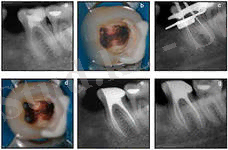

Рентгендік тексеру емдеу әдісін дұрыс таңдау мен сол арқылы асқынулардың алдын алуға мүмкіндік береді. Тістердің түбірлерінің қалыптасу және сорылу мерзіміне сүйене отырып пульпитті емдеуде көрсетілімдерді таңдауда мышьяк пастасын қойғаннан кейінгі перипикалды аймақта әр түрлі асқынулардың алдын алу үшін сүт азу тістерін 8-9 жаста жұлу керек. Сүт күрек тістерде пульпит некроз және ұлпаның өлуі салдарынан өте сирек кездеседі. Олар созылмалы периодонтитпен асқынады. Ұлпа қабынуын емдеу әдісін таңдауда бірінші кезекте қабынудың таралуы және түбір өзегін сипаттайтын анатомиялық талаптан кейін тістің жағдайын және баланың жалпы жағдайы маңызды болып табылады. Ұлпаны жасанды некрозды шақырып немесе иньекционды жансыздандыруды қолданып жансыздандырады (ұлпа қабынуын девиталды және виталды емдеу әдістері) .

Жедел пульпитті емдеу

Сүт тістердің ұлпасының жартылай қабынуында негізгі емдеу әдісі ұлпаның сауыт бөлігін ампутациялау болып табылады. Виталды ампутация - көрсетілімдеріне алдымен дамуы әлі бітпеген тістер жатады. Түбір дамуы бітпеген немесе шамалы кірген, тарылған түбірлері бар үлкен азу тістерге девиталды ампутацияны қолдануға болады. Девиталдаушы құрал ретінде сүт тістерге мышьяк ангидридін қолданбау керек. Оның орнына әлсіз жәй әсер ететін девиталдаушы құралдарды қолдануға болады. Тісжегілі (кариозды) қуысында оны жеті күн шамасында қалдырады. Девиталды ампутациядан кейін ұлпа шолақ бөлігін (культясын) мумифицирлейтін пастамен жабады (резаорцин-формалинді) және тісті пломбалайды. Жалпы пульптті емдеуде барлық ұлпаны алып тастау керек (экстирпация) осы араласуды девиталдаудан кейін түбір өзегін химиялық және механикалық дайындау үшін оларды сорылмайтын (нерассасывающий) пастамен толтырады.

Созылмалы пульпитті емдеу

4 жасқа дейінгі жоғарғы күрек тістерде және төменгі үлкен азу тістерде дамитын, туа біткен тіс тінінің даму кемістігі бар тістерде бірінші реттік созылмалы пульпиттер басым болады. Бұл жағдайда витальды ампутацияны қолданады. Өршіген біріншілік созылмалы пульпитте бұл жаста тіс түбірлері қалыпталмаған тұрақты тістердің дайын үлгісі (заготовкасы) максималды жақындаған. Ұлпа камерасының қуысы кең, түбір өзектері кең және қысқа болады. Ұлпа тіні морфологиялық және функционалды толмаған пульпитті емдеу ұлпа мумификациясымен 3 қабылдауда девиталды ампутацияны қолданады. 4-6 жаста жедел пульпит пайда болады. Тіс түбірлері бұл кезде қалыптаспаған (тікелей және тікелей емес жабық ұлпалар) . Балаларда экстирпация әдісімен пульпитті емдеу Көрсетілімдері: жедел іріңді, созылмалы гангренозды, периодонтта фокальды өзгерістері бар барлық пульпиттер және барлық түбір ұлпасын сақтауға мүмкін болмағанда қолданылады. Балаларда тек түбірдің өсуі аяқталғанан кейін және түбір ұшты кеңістік қалыптасқанан кейін толық алып тастайды. Уақытша тістерде тек қалыпталған түбірлерді алып тастайды.